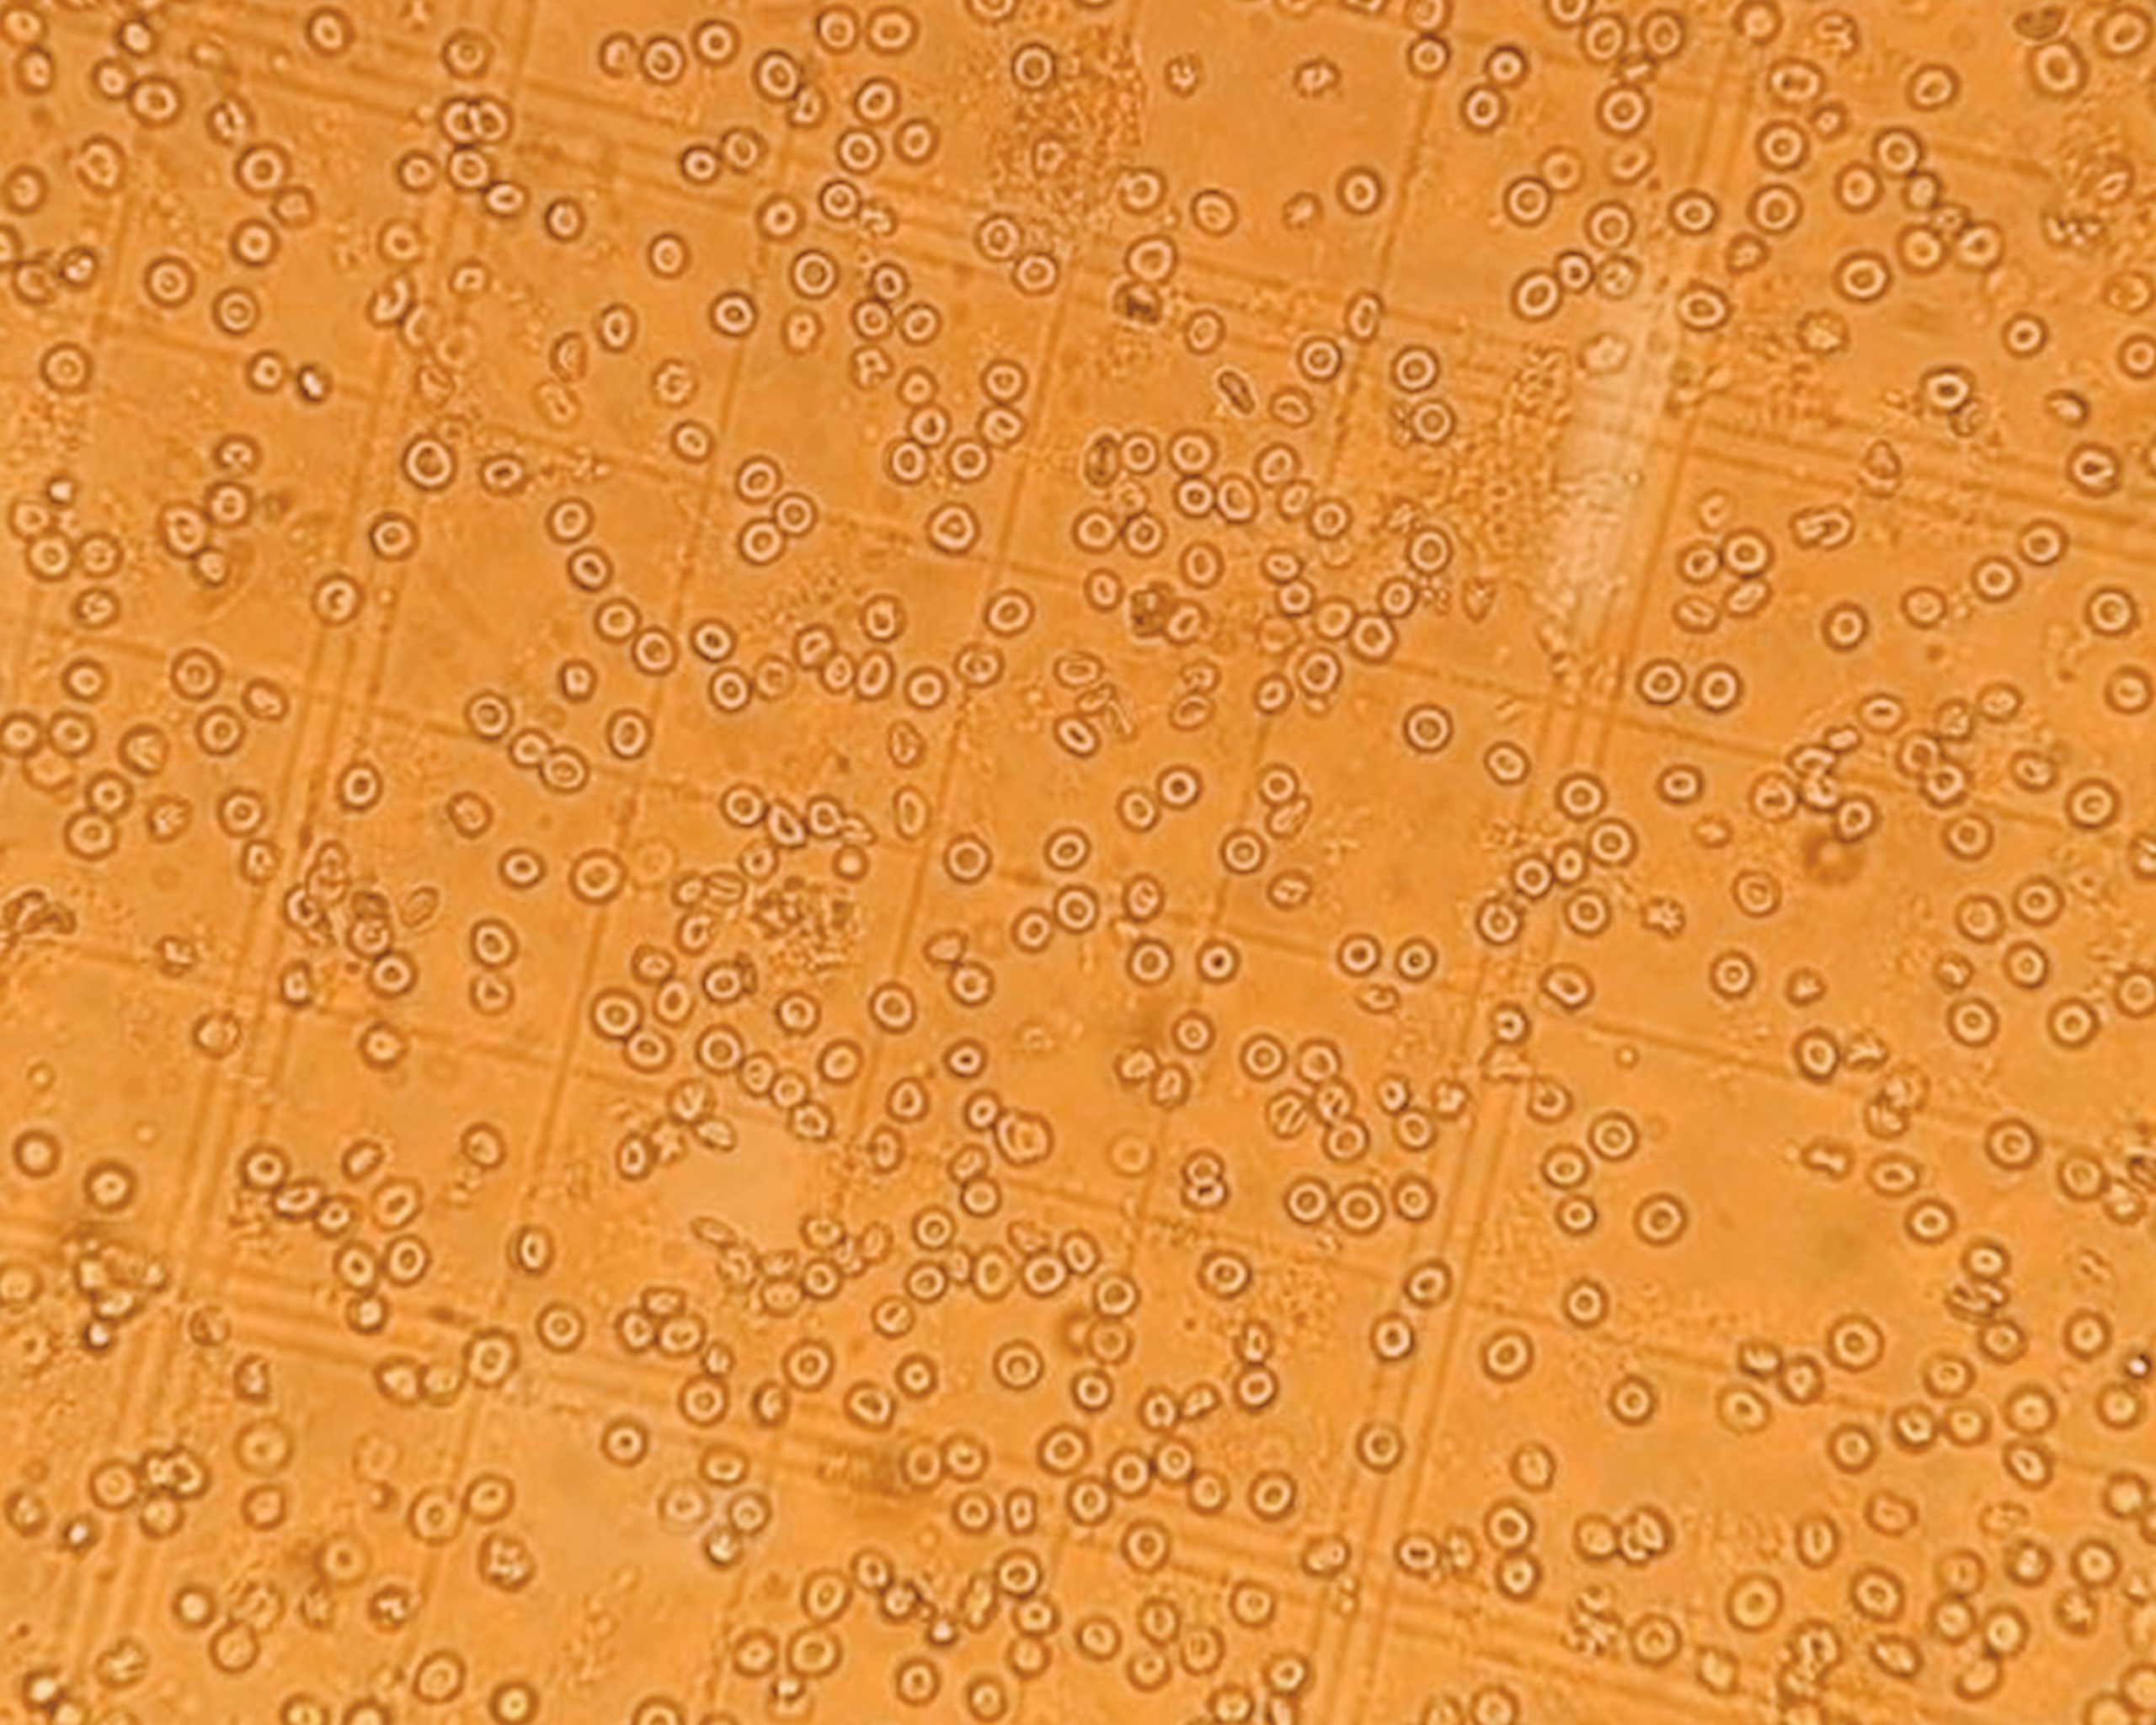

ChemPartner offers a variety of pre-clinical models for MS study, designed to help researchers explore disease mechanisms, immune modulation, and treatment response.

• How MS models capture neuroinflammation, demyelination, and disease progression